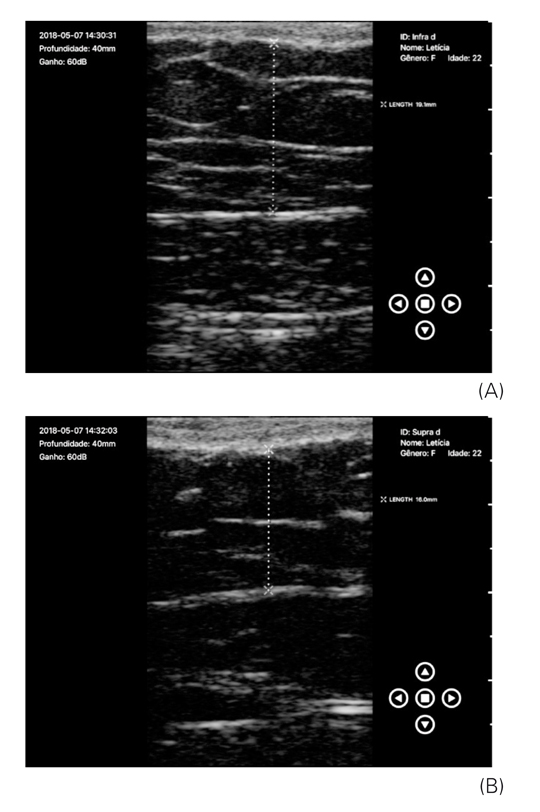

Verificou-se que, no momento inicial nas avaliações das medidas supra e infraumbilical, já existia uma diferença, fato que dificultou a interpretação dos resultados na avaliação final, quando também se observou uma diferença entre as zonas supra e infraumbilical esquerda. Mas ao analisar as imagens de ultrassonografia individualmente, é possível perceber a diferença entre as regiões tratadas e controle, conforme demonstra as Figuras 3A e 3B (análises ultrassonográficas da região infra e supraumbilical esquerda antes do tratamento), Figuras 4A e 4B (análises ultrassonográficas da região infra e supraumbilical direita, controle), Figuras 5A e 5B (análises ultrassonográficas da região infra e supraumbilical esquerda após tratamento) e Figuras 6A e 6B (análises ultrassonográficas da região infra e supraumbilical direita após tratamento, controle).

(A) Análise ultrassonográfica da região infraumbilical direita, após tratamento, lado controle, 1,91 cm; (B) Análise ultrassonográfica da região supraumbilical direita, após tratamento, lado controle, 1,60 cm

Os autores.

Por meio das imagens de ultrassonografia demonstradas nas Figuras 3 e 5 e dos dados contidos na Tabela 2, verificou-se que a região tratada teve uma redução importante, comparada com a do lado controle, de 0,6 cm na região infraumbilical e 0,15 cm na região supraumbilical. Do total da amostra, 21 mulheres apresentaram esse comportamento, assim a diferença sempre foi mais acentuada na região infraumbilical, na qual o aplicador da TOC foi utilizado de forma estacionária. Mas no lado controle, percebeu-se que a região infraumbilical não se alterou após o período de quatro semanas e na região supraumbilical a redução foi 0,14 cm, em uma voluntária. Em seis participantes, a região supraumbilical não apresentou redução. Não foram feitas análises em quatro mulheres, pois estas não realizaram o exame final. A análise foi feita pela avaliação do ultrassonografista.